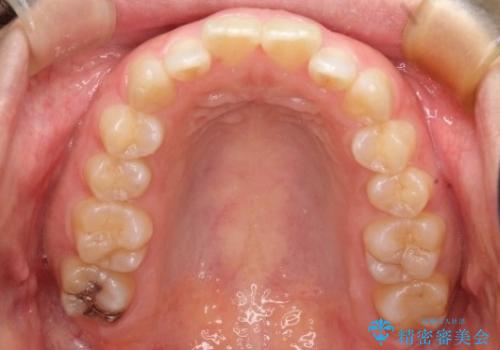

初診時の歯並びの状態としては、上の前歯が下に対して前に飛び出た上顎前突という状態で、前歯は大きく前に飛び出した状態により患者様も口の閉じづらさを感じているとのことでした。また上顎に軽度の叢生(ガタガタ)がありました。

抜歯は行わず上顎の奥のスペースを利用して歯をスライドする方法の他に歯列弓の拡大やディスキング(歯と歯の間の隙間を作る処置)を行い叢生を改善しました。

奥歯を後ろに送る工程では上下でゴムかけをしていただきました。